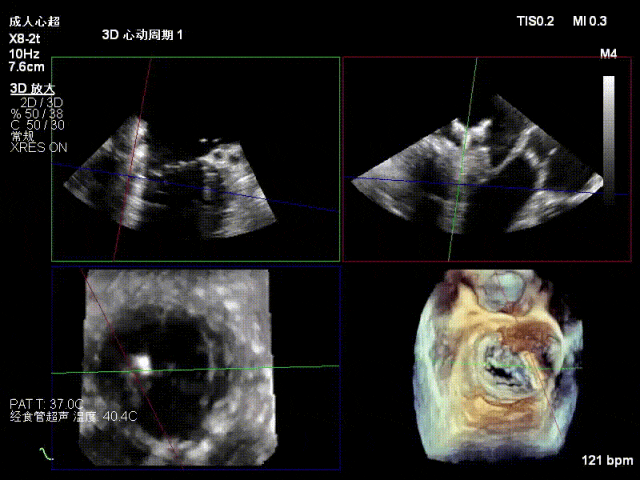

术中超声(关键步骤)

混合性MR,P2脱垂连枷(脱垂范围15mm,连枷间距4mm),腱索断裂

新分型:ACA型,反流2区及两侧,MR 4+,VC:3×14mm

A2:24mm,P2:17mm,AP:38mm,MVA约5.7cm²